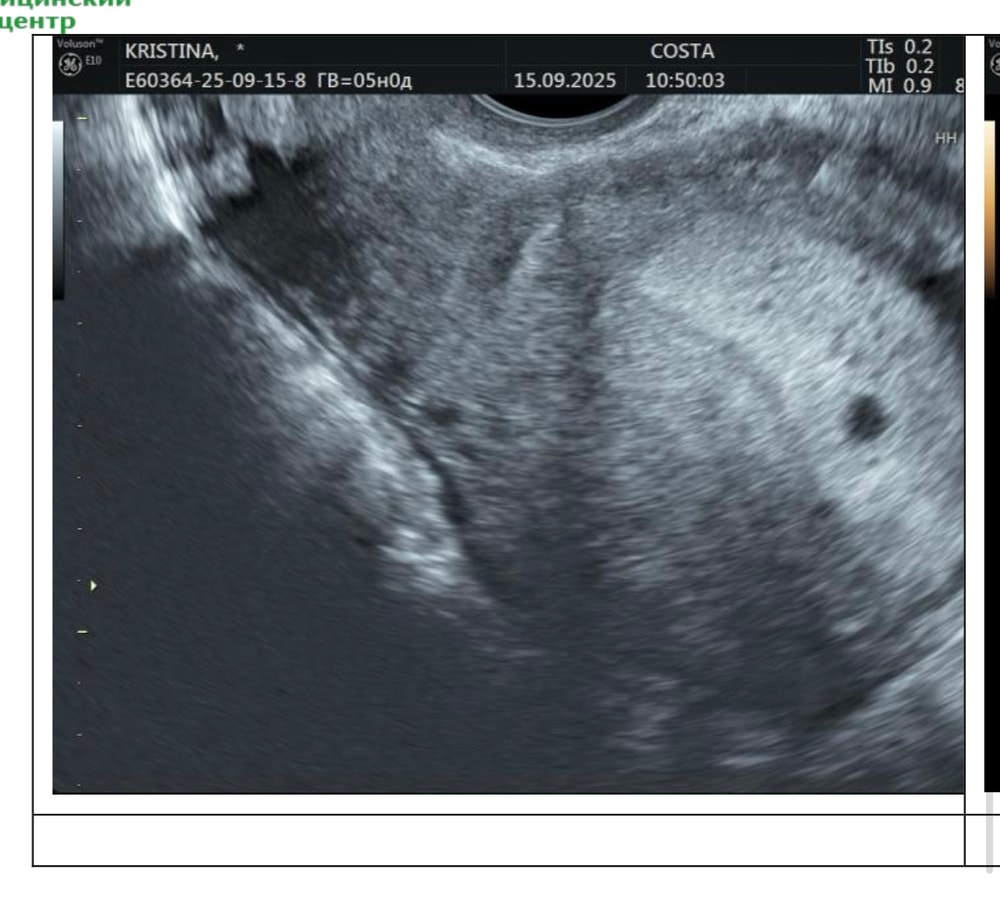

Мы тут все не узисты, но невооруженным глазом видно ПЯ. Срочно меняйте врача, так могут и до инфаркта довести, а не дай бог и до чистки здорового ребенка

Я бы на вашем месте пошла в другую клинику на УЗИ, очень многое зависит от аппарата и самого врача. У вас хороший эндометрий, и судя но фото УЗИ видно плодное яйцо🙏🏻🥰

Вот мое узи при хгч примерно 1500, уже не помню, 15го сентября было узи, 17го хгч был 3500, больше не сдавала. ПЯ по узи 4,2мм 🙌🏻☺️Ваше «образование» это и есть пя. Обходите эту клинику стороной

Крис, сегодня переделала в другом месте , плодное яйцо 5 мм, увидели тут же , были в шоке от этого узи , что там понаписали , сказали картина 5 недели беременности

Эндометрий шикарный. Я неделю назад делала узи на 5 неделе у меня эндометрий был 19.6мм. Смените врача и сделайте другое узи.

Альбина, она мне вообще сказала в такой эндометрий имплантация невозможна , а какая имплантация , если хгч растет

Анжелика , я побелела вообще на этом узи, не понимаю , задержка , хгч растет , а мне говорят с таким эндометрием идите на чистку , увидела что то, говорит глаз цепляет, но в твоем эндометрии не разобрать что это

А то такие Вас до инфаркта доведут. Прекрасно можно разобрать, что на 1 фото ПЯ. Понасажают в кресло "специалистов", блин

Видно же пя) пересдайте разок хгч, и сходите на узи где аппарат получше.